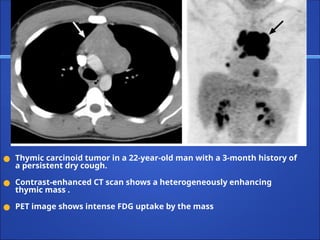

● Thymic carcinoid tumor in a 22-year-old man with a 3-month history of

a persistent dry cough.

● Contrast-enhanced CT scan shows a heterogeneously enhancing

thymic mass .

● PET image shows intense FDG uptake by the mass